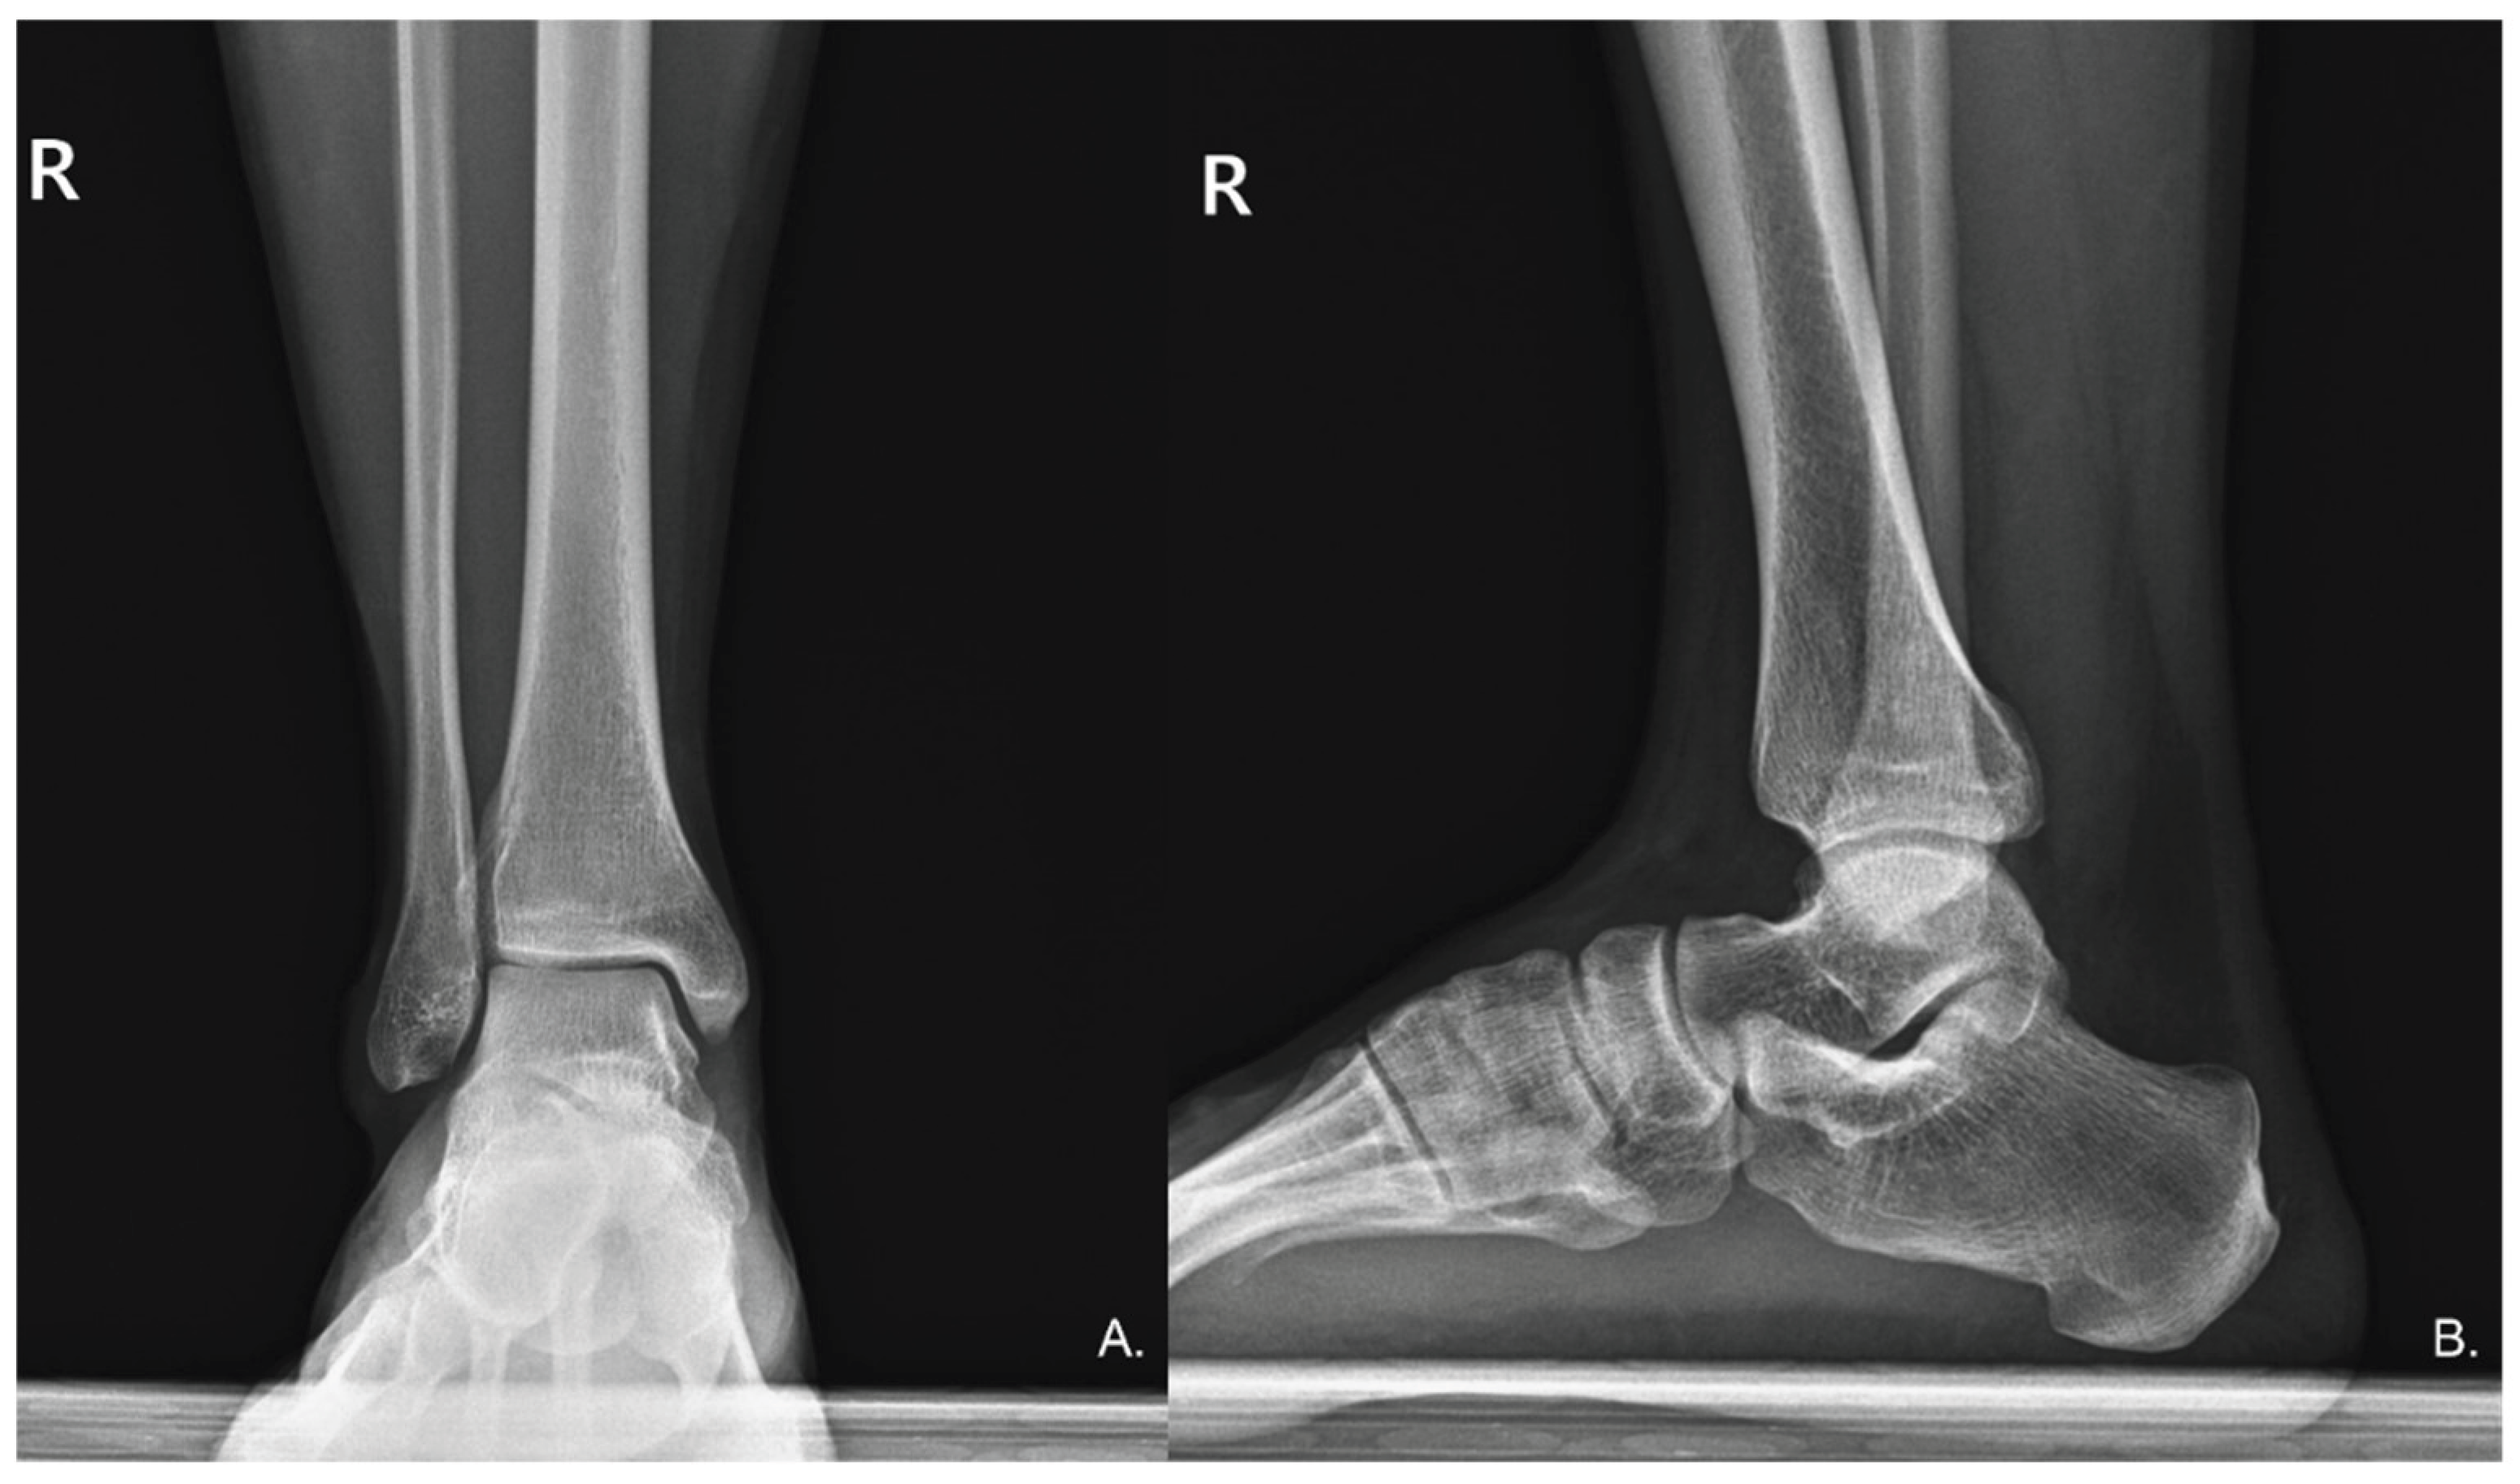

2. Case Presentation

2.1. Diagnosis of Sural Nerve Entrapment Using Sonoguide Digital Palpation